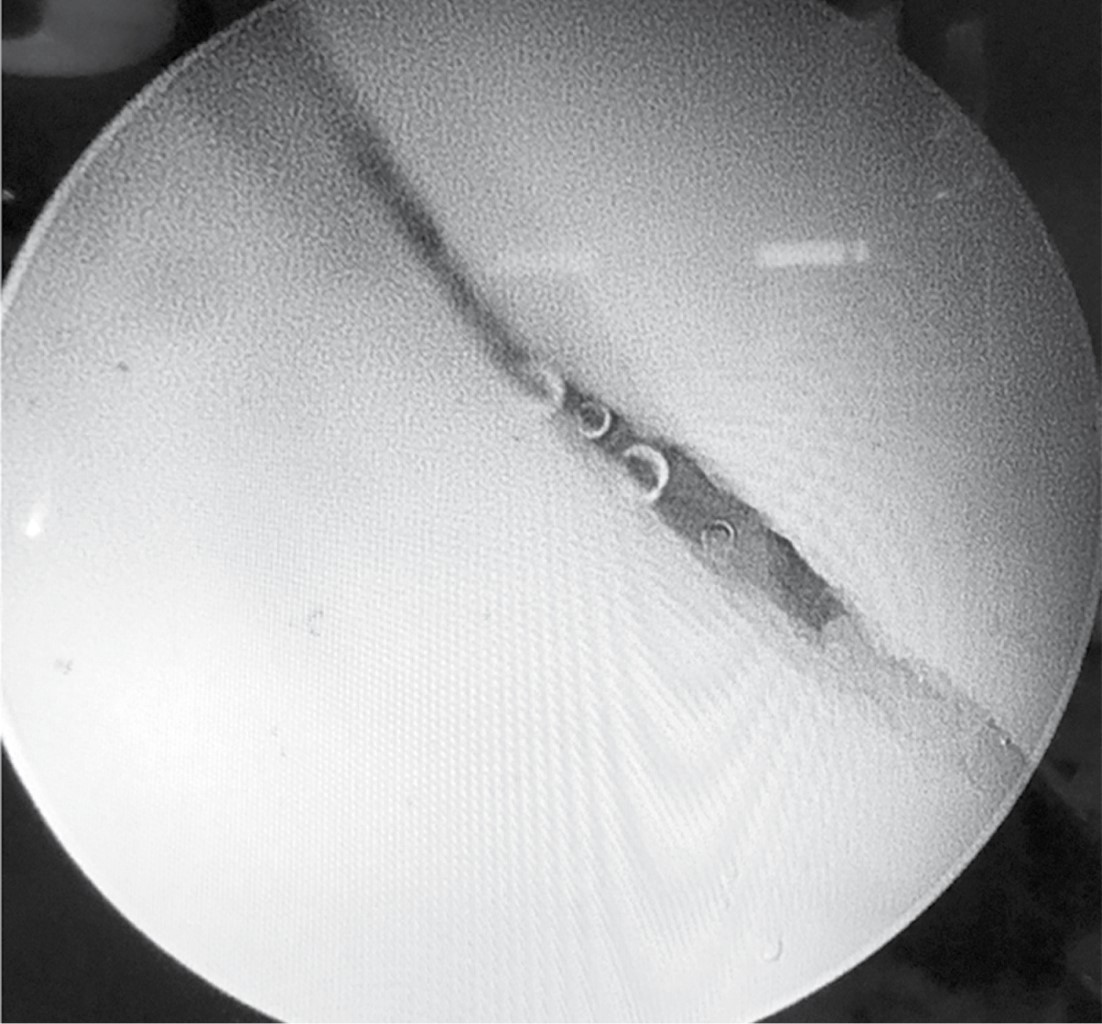

Al realizar la tracción de miembro pélvico izquierdo se logró la subluxación con apertura del espacio articular coxofemoral necesario para la introducción del material artroscópico. Por el portal anterolateral se introdujo el lente de 70 grados para visualización intraarticular. Se localizó con visión intraarticular el portal anterior estándar para introducción de material de trabajo. En la exploración articular se observó hemartrosis con sinovitis inflamatoria, se realizó lavado intraarticular y hemostasia, se extrajeron fragmentos libres de cartílago con punta de rasurador. Se localizó lesión traumática de labrum en región posterior acetabular, la cual se estabilizó con radiofrecuencia, se ubicó el trazo de fractura acetabular en columna posterior longitudinal simple con separación de 4 mm (Figura 4). Se realizó abordaje de 4 cm en primera ventana de Judet y se disecó por planos hasta localizar con guía canulada el punto de entrada para la colocación de tornillo de compresión, asistido por fluoroscopía de 7.0 mm por 85 mm y bajo visión directa intraarticular para observar el cierre del trazo de fractura con congruencia articular satisfactoria (Figura 5). Finalmente se procedió a la extracción de instrumental artroscópico y cierre de heridas por planos.

Evolución posquirúrgica: con un movilizador pasivo de cadera se efectuó de manera inmediata en el posquirúrgico la movilización, logrando flexión de 90 grados sin dolor. En el primer día de postquirúrgico se egresó a la paciente con apoyo diferido por ocho semanas. A las 12 semanas, el control radiográfico se observó con adecuada consolidación, la paciente, por completo asintomática, logró realizar la marcha con carga completa y con arcos de movilidad normales en la cadera intervenida. Se aplicó la escala Harris Hip Score,32 obteniendo un resultado de 91, considerado como excelente (Figura 6).

Figura 5